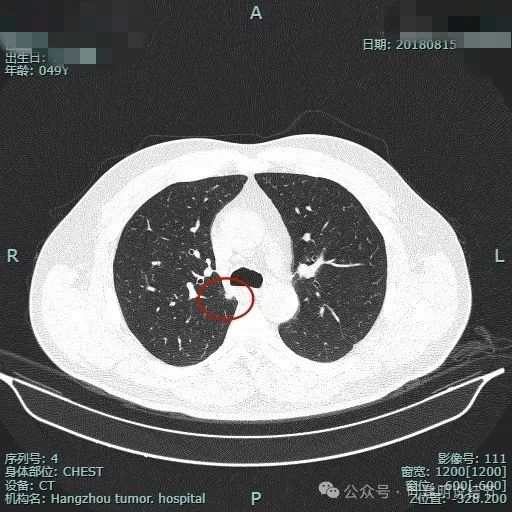

再看2018年时连续层面的:

病灶出现。

实性密度,边缘略糊。

表面毛刺。

紧贴胸膜。

血管进入。

整体轮廓较清。

细毛刺明显。

缺乏膨胀性。

边缘区密度较淡。